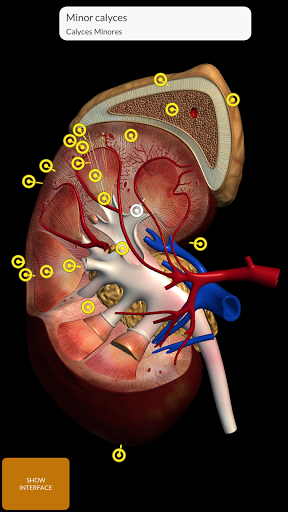

Grâce à une interface simple et intuitive, il est possible d'observer chaque structure anatomique sous n'importe quel angle.

Les modèles anatomiques 3D sont particulièrement détaillés et avec des textures jusqu'à une résolution de 4k.

La subdivision par régions et les vues prédéfinies facilitent l'observation et l'étude de parties individuelles ou de groupes de systèmes et les relations entre différents organes.

• Système urogénital (homme et femme)